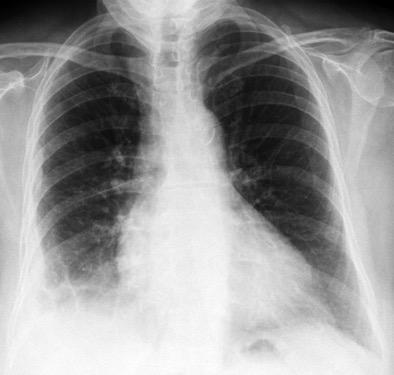

Marzo 2014: Perforación longitudinal distal secundaria a episodio de vómito (síndrome de Boerhaave). Derrame pleural izdo. que evoluciona a empiema.

Wang C-T et al. Tension hydropneumothorax in a Boerhaave syndrome patient: A case report . World J Emerg Med, 2021. Katabathina V et al. Nonvascular, nontraumatic mediastinal emergencies in adults:a comprehensive review of imaging findings. Radiographics. 2011.